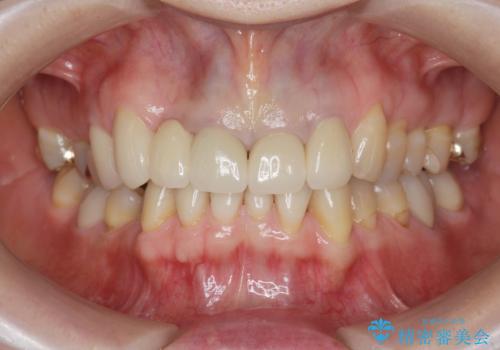

境目の見える前歯をきれいにしたい セラミック治療

自然な歯の色調や仕上がりに大変満足いただけました。

- 66万円(ジルコニアクラウン×5・仮歯×5)費用は治療当時の料金となります